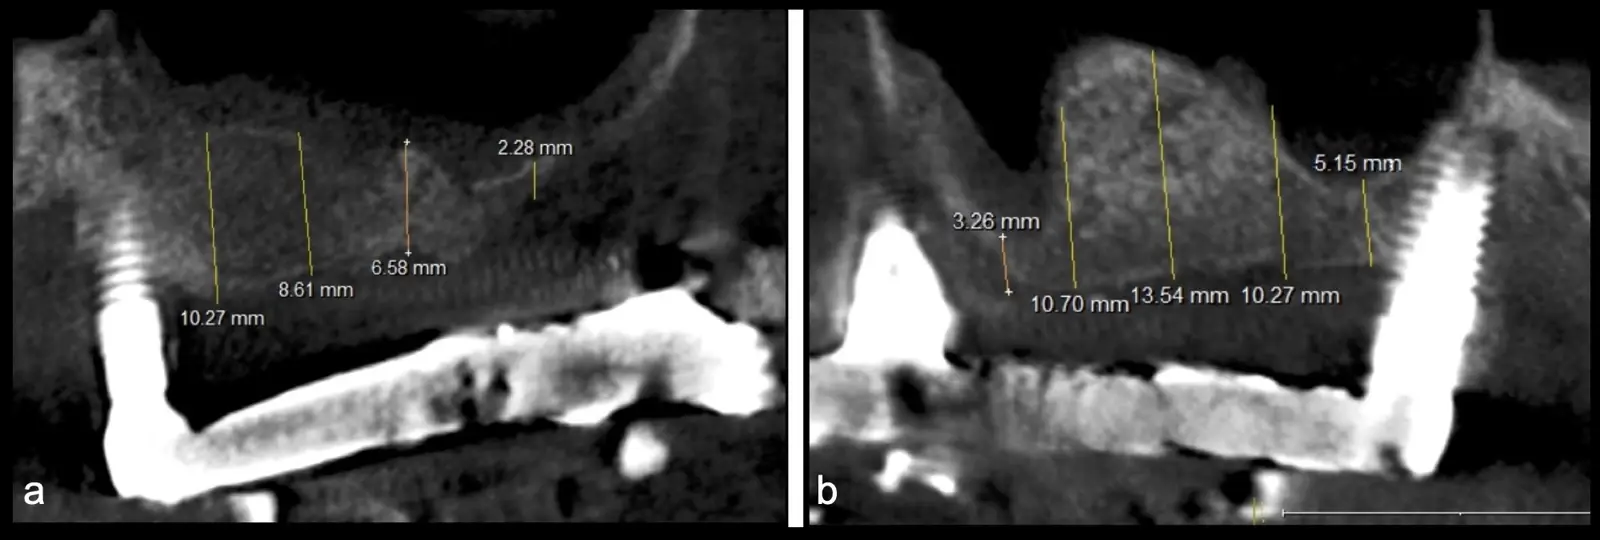

El levantamiento de piso de seno maxilar es una técnica quirúrgica aceptada previa o simultáneamente a la colocación de implantes dentales. La mayor evidencia científica refiere que si se tiene entre 0 -7 mm de altura ósea se debe realizar la elevación sinusal junto con injertos óseos; y a partir de los 8 mm, se hace más predecible la colocación simultánea de implantes dentales.1-3

El clínico puede retirar la tabla ósea o introducirla como “tienda de campaña” dentro del seno maxilar. En cualquiera de las alternativas, es importante evaluar la presencia de tabiques óseos y de la arteria postero alveolar superior.